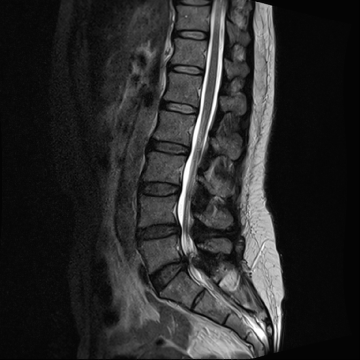

요추 협착증 수술 전·후

2022.08.11

2022.08.16

ㆍ환자 동의를 받은 자료이며, 이미지 사진은 실물과 다를 수 있습니다.

ㆍ모든 자료는 새움병원 자료입니다.